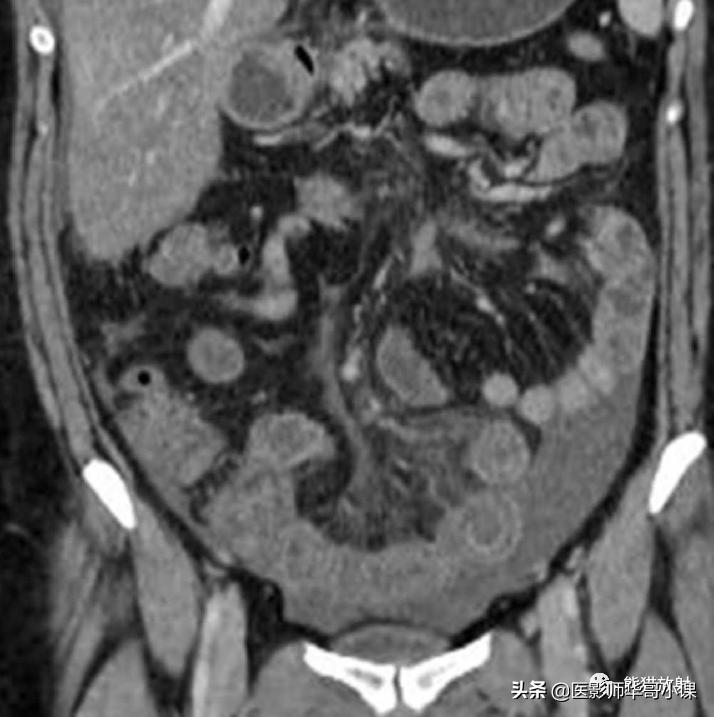

肠系膜脂膜炎的特征性CT表现 为肠系膜根部边界清晰、密度不均的脂肪肿块,包绕肠系膜血管,可推移或不推移邻近肠襻,但不侵犯邻近肠襻,血管周围可见低密度环(图)。T2WI上呈低信号包膜,静脉注射对比剂后可见强化。

回缩性肠系膜炎CT表现 为浸润性软组织密度肿块,周围可见放射状条索影(图),这些特点可能与纤维瘤病或类癌相似。 硬化性肠系膜炎 在T1WI和T2WI图像上均呈低信号,有助于疾病的鉴别。肿块中央坏死区可见钙化(图)。该病有一定的自限性,通常预后较好。

肠系膜脂膜炎。患者腹痛,增强CT(A)和真实稳态进动快速成像(true-FISP) MRI(B) 显示一个边界清晰的脂质肿块(大箭),从小肠系膜根部向左侧腹部延伸,包绕肠系膜血管,无扭转。注意血管周围的晕环(小箭)

纤维性肠系膜炎。不明原因发热患者,增强CT显示边缘不规则纤维脂肪样肠系膜肿块包绕肠系膜血管。从肿块到相邻的肠系膜脂肪可见放射状软组织条索影。

纤维性肠系膜炎。CT表现增强CT显示大而边界模糊、广泛钙化的肠系膜软组织肿块。注意邻近的肠襻回缩及增厚。